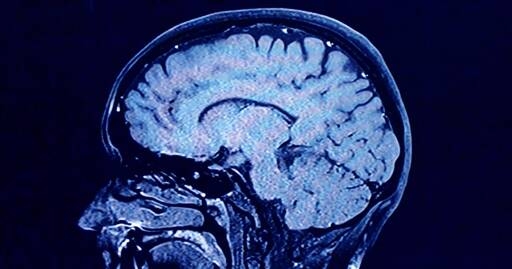

As we age, the human brain rewires itself. The process happens in distinct phases, or “epochs,” according to new research, as the structure of our neural networks changes and our brains reconfigure how we think and process information.

For the first time, scientists say they’ve identified four distinct turning points between those phases in an average brain: at ages 9, 32, 66 and 83. During each epoch between those years, our brains show markedly different characteristics in brain architecture, they say.

The findings, published Tuesday in the journal Nature Communications, suggest that human cognition does not simply increase with age until a peak, then decline. In fact, the phase from ages 9 to 32 is the only time in life when our neural networks are becoming increasingly efficient, according to the research.

During the adulthood phase, from 32 to 66, the average person’s brain architecture essentially stabilizes without major changes, at a time when researchers think people are generally plateauing in intelligence and personality.